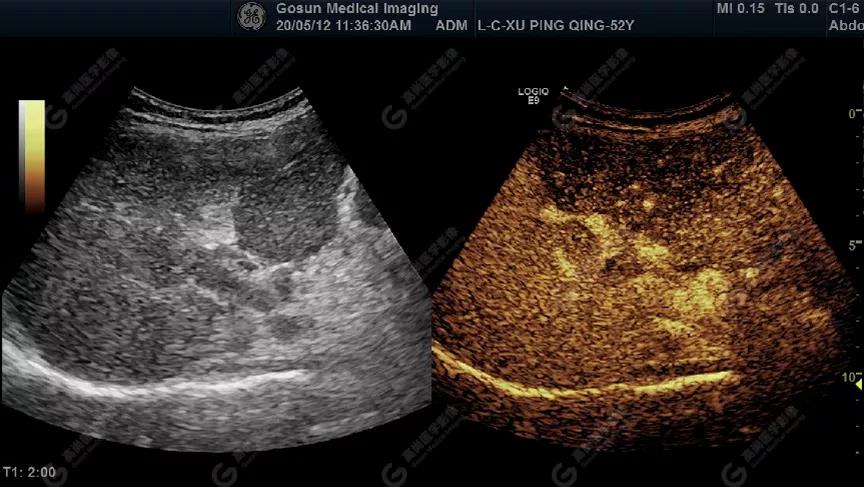

為進(jìn)一步明確診斷,超聲檢查醫(yī)師與該男士進(jìn)行溝通后,隨即為其進(jìn)行超聲造影檢查

超聲造影顯示門靜脈內(nèi)低回聲呈高增強(qiáng)

延遲期肝S7局部回聲減低,范圍約82mm×50mm

內(nèi)見(jiàn)范圍約13mm×16mm低增強(qiáng)區(qū)

超聲所見(jiàn)肝包膜不光滑,實(shí)質(zhì)回聲增粗,不均勻,以右葉顯著,肝內(nèi)可見(jiàn)散在高回聲結(jié)節(jié),最大約7mm×5mm,邊界清,形態(tài)規(guī)則,CDFI顯示高回聲結(jié)節(jié)未見(jiàn)明顯異常血流信號(hào)。門靜脈主干內(nèi)徑約14mm,門靜脈右支管腔內(nèi)見(jiàn)實(shí)性低回聲,大小約23mm×14mm,邊界不清,形態(tài)不規(guī)則,局部與肝組織分界不清,CDFI:門靜脈主干血流緩慢,左支血流充盈好,右支血流充盈缺損,低回聲內(nèi)未見(jiàn)明顯血流信號(hào)。超聲造影:經(jīng)左側(cè)肘靜脈團(tuán)注超聲造影劑sonovue2.0ml。肝組織開始增強(qiáng)時(shí)間8秒,病灶開始增強(qiáng)時(shí)間11秒,邊界清晰。脈期呈均勻高增強(qiáng),至門脈期和延遲期消退為低增強(qiáng)。延遲期肝S7段局部回聲減低,范圍約82mm×50mm,內(nèi)見(jiàn)一低增強(qiáng)區(qū),范圍約13mm×16mm。

超聲提示門靜脈內(nèi)實(shí)性占位病變(考慮癌栓可能)

肝S7段異常回聲(不排除原發(fā)性肝Ca,建議進(jìn)一步檢查)